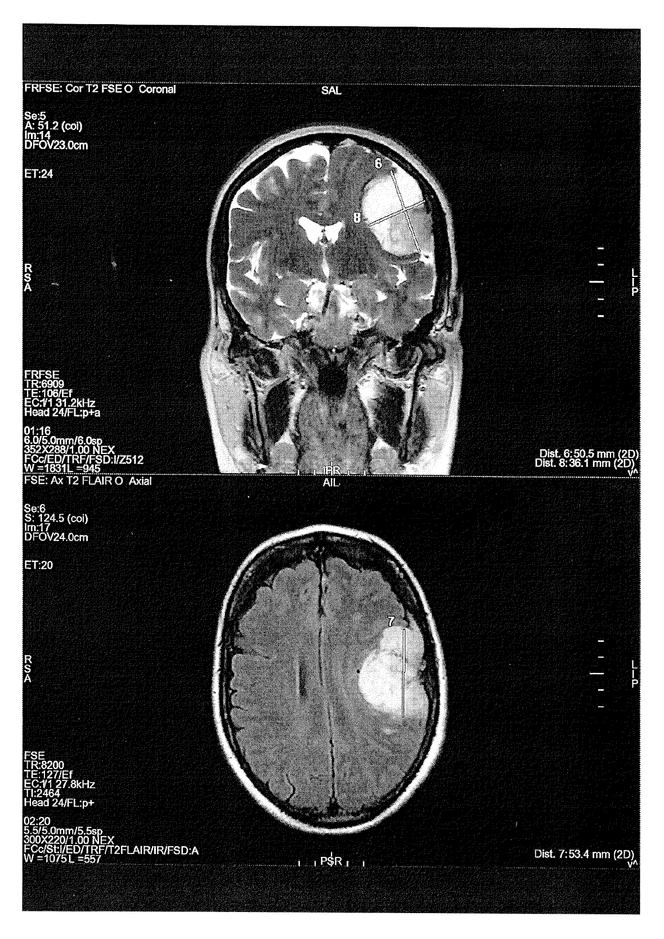

Une IRM montrant un méningiome provoqué chez une victime par la prise d’un progestatif. DOCUMENT LE MONDE Un nouveau front judiciaire s’ouvre dans l’affaire de l’Androcur,cette pilule miracle prescrite pendant des années pour traiter l’endométriose,l’acné,la chute de cheveux ou encore comme moyen de contraception,mais à l’origine de tumeurs du cerveau (méningiomes) chez des centaines de femmes. Selon les informations du Monde,une plainte contre X a été déposée mardi 5 novembre devant le tribunal judiciaire de Paris par l’Amaeva,l’association qui regroupe les victimes de l’Androcur et des autres traitements hormonaux dérivés de la progestérone (Lutényl,Lutéran…). Elle vise cinq infractions pénales : administration de substance nuisible,atteinte involontaire à l’intégrité de la personne,mise en danger d’autrui,non-signalement d’effet indésirable,tromperie aggravée.

Elles racontent toutes les mêmes histoires. Des gynécologues ou des endocrinologues qui prescriventle médicamentsans alerter les patients du risque de méningiome,l’apparition de symptômes (céphalées,troubles de la vision…),la découverte de tumeurs à la suite d’IRM du cerveau,une intervention chirurgicale à risque pour retirer des tumeurs,des séquelles invalidantes (fatigue,maux de tête,perte de la vision ou auditive,troubles neurocognitifs,épilepsie…) plusieurs années après l’opération.